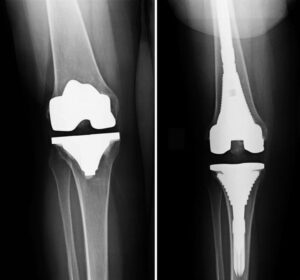

Joint replacement surgery is recommended when severe joint damage causes persistent pain, stiffness, or loss of mobility that interferes with everyday life. Revision surgery is required when a previous joint replacement no longer functions properly due to wear, loosening, infection, or implant failure. With modern surgical techniques and improved implant designs, both procedures can deliver long-lasting pain relief and restored joint function.

Treatment Options for Joint Replacement & Revision

-> Hip replacement ->Knee replacement ->Shoulder replacement ->Advanced implant techniques